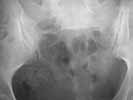

Subject: U-shaped sacral fracture

This is an 18 year old healthy women roll-over ATV with femur fracture now with an antegrade nail. Can I have your advice about this U-shaped pelvis fracture? Injury was pm 5/29.

It appears to be a U-shaped sacral fracture on the limited studies/images...the anterior ring is not shown.